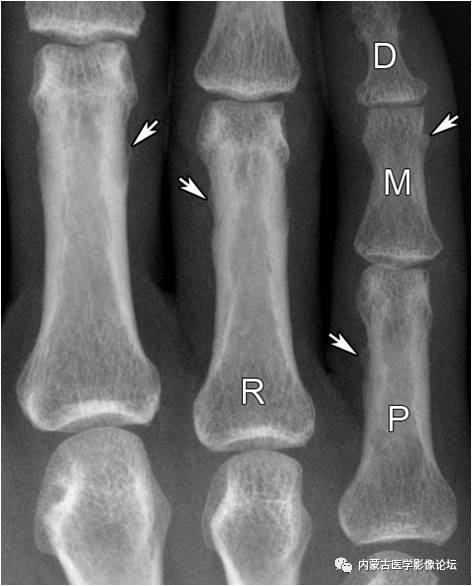

指骨骨皮质增厚:近、中节指骨骨皮质厚而致密,骨髓腔变窄,无病理学意义。

指骨正常骨突与骨嵴:白箭所示为肌腱附着的骨突与骨嵴,不应误为骨痂或骨膜增生。R:环指,P:近节指骨,M:中节指骨,D:远节指骨。